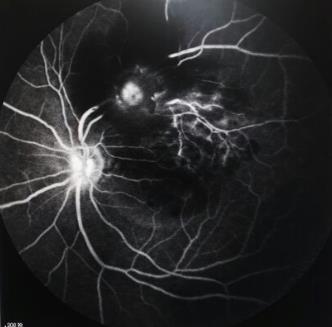

视网膜大动脉瘤(2):它的眼底,oct,自发荧光和icg反射影像特点

【眼底病讨论】多发大动脉瘤伴微动脉瘤 [病例帖]

【眼底病讨论】"视网膜大动脉瘤"回头看(12月4日更新mri) [精华]

「临床研究」视网膜大动脉瘤的多模式眼底影像特征